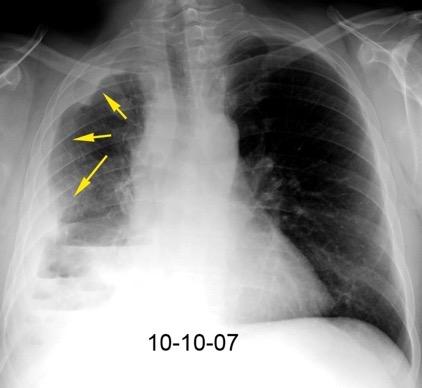

40. EMPIEMA PLEURAL. ORIGEN HEPÁTICO